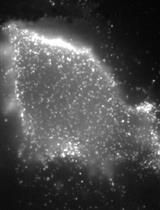

Circulating anti-dsDNA antibody is a hallmark of SLE both in human patients and in many SLE mouse models. This protocol describes how to measure the frequency of plasma cells producing these antibodies in the spleen of lupus-prone mice. This protocol was developed or modified in Dr. Anne Davidson’s lab at Feinstein Institute for Medical Research.

Liu, Z. (2011). ELISpots Assay to Measure the Number of Murine Plasma Cells Producing Anti-dsDNA Antibodies. Bio-protocol 1(24): e34. DOI: 10.21769/BioProtoc.34.